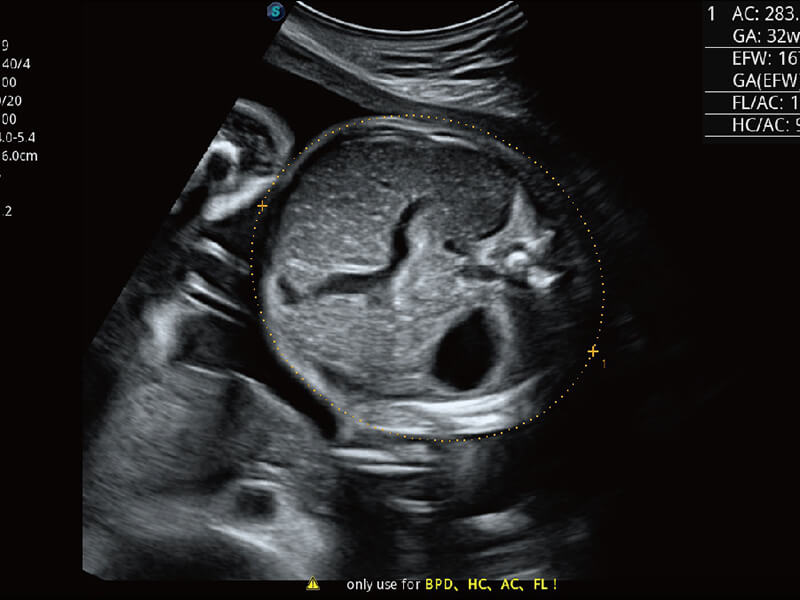

S60探头工艺,从前端信号处理每一个环节采集无损声学数据,真实还原组织原貌,再现解剖细节。

S-Fetus 产科扫查助手

高分辨率容积成像 栩栩如生

超宽频带技术,为容积成像带来优质的二维图像基础,为您呈现丰富的结构细节,栩栩如生地展示宝宝的宫内形态以及各种组织的立体结构。